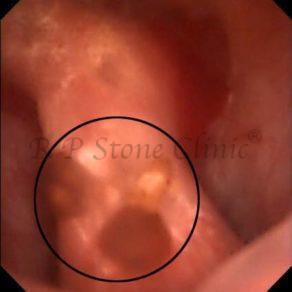

Kidney stone is a solid mass of CRYSTALS. It is the process of crystallization which initiates the formation of kidney stones. This happens in nephrons or units of kidney. Once a small crystal is formed, it can both grow & unite with other crystals leading to the formation of small concretion which eventually forms a stone. Once these large crystals detach from the collecting ducts, the process of stone formation starts in the renal collecting system. A recurrent kidney stone former is advised to know a little bit about something known as Randall’s plaque. Alexander Randall discovered plaques on the renal papillae eight decades back based on examination of 1154 pairs of autopsied Kidneys. He described these renal papillary lesions as cream colored or milk patch areas composed of calcium phosphate & calcium carbonate. These plaques could act as NIDUS for formation of KIDNEY STONE. Calcium Oxalate stone can form on this nidus & then detaches from this plaque to become a free floating stone in the collecting system of kidney

These images are taken as snap shots from the video recording of RIRS Surgery done at our hospital. These are Randall’s Plaques seen with Digital FLEX XC & Digital FLEX XC S. The cream or whitish patches are seen on the tips of RENAL PAPILLAE as seen in images below.

Randall’s Plaques may lead to the formation of Stones.

Those kidney stone patients who have Randall’s Plaques in their kidneys are more likely to form stones again (Recurrent Stones).

Stone Patients in whom Randall’s Plaques are detected at the time of RIRS Surgery should undergo regular ultrasound examination for early detection of stones.

Patients of Stones with Randall’s Plaques in their Kidneys should drink plenty of fluids in addition to Orange Juice & Lemonade.